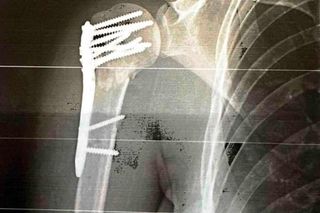

Obecnie gwiazda "Dzień Dobry TVN" zaczyna powoli wracać do zdrowia. Przed nią jest jednak jeszcze długa droga. Na szczęście może liczyć na bliskich. Cztery dni po operacji wrzuciła kolejny post na Instagram. Wyznała w nim, że zmaga się z ogromnym bólem. Lekarze musieli wczepić jej aż dziewięć śrub, dzięki którym trzymają się kości prawego ramienia.

Dziś mija 4 doba od operacji i 4 najgorsza w moim życiu pod względem bólu, który w skali 1-10 oceniam na 15. Finalnie zamiast trzech blach mam dziewięć śrub i codziennie faszeruję się lekami przeciwbólowymi, żeby jakoś wytrzymać - napisała.

Ten pan ma teraz pamiątkę w postaci filmiku z wyjazdu, a ja mam pamiątkę w postaci dziewięciu śrub - podsumowała Aleksandra Rogowska-Lichnerowicz.